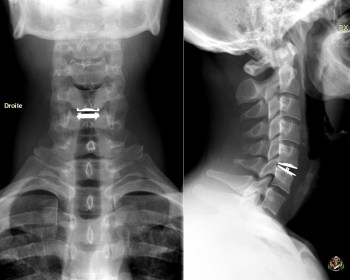

The limited cervical disc herniation which did not improve with the conservative treatment and with a limited cervical arthritis, is the ideal indication for the cervical prosthesis.

A prosthesis could be inserted in a more severe uncodiscarthritis if during the procedure a circumferential resection of the arthritic tissue is possible.

The placement of prosthesis does not require any additional contention; the functional recuperation is quick and this procedure seems to been interesting on the positive socio-professional level.